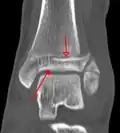

A triplane fracture of the ankle as seen on plain X-ray -

A triplane fracture of the ankle as seen on CT -

A triplane fracture of the ankle as seen on CT

- Triplane fractures are a special type of fracture that involves the immature skeleton. It has a coronal plane in the metaphysis, an axial plane in the physis, and a sagittal plane in the epiphysis.[15]